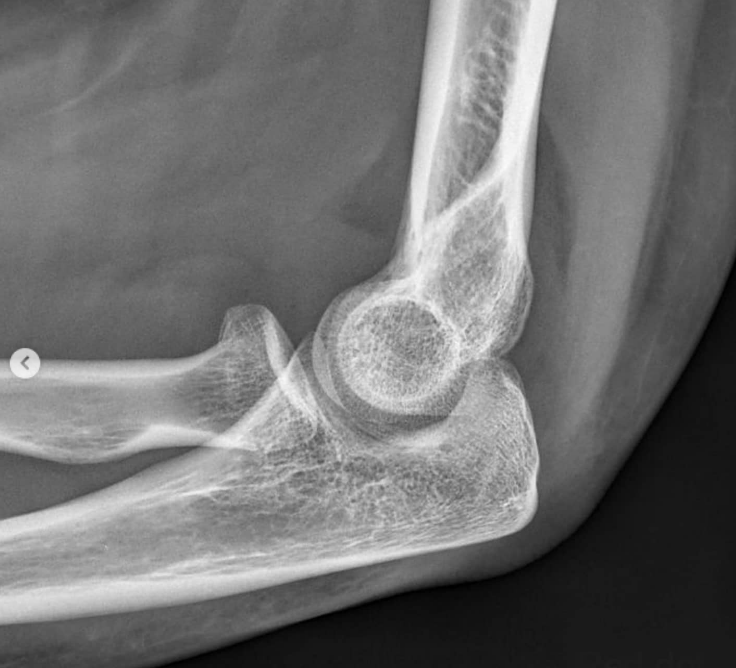

Lateral:

Signo de la almohadilla grasa (fat pad sign): grasa desplazada anterior y/o posterior → indica derrame articular → sospechar fractura oculta

Línea radiocapitelar: debe pasar por el centro del capítulo (si no → luxación de cabeza radial)

Olécranon en fosa olecraniana

Línea radiocapitelar

¿Qué es la línea radiocapitelar y para qué sirve? (teórico clínico | poca relevancia)

Línea trazada a lo largo del eje longitudinal del radio

En TODA proyección de Rx debe pasar por el centro del capítulo

Si no pasa → la cabeza del radio está luxada

Fundamental para diagnosticar Monteggia (fractura de ulna + luxación de cabeza radial)